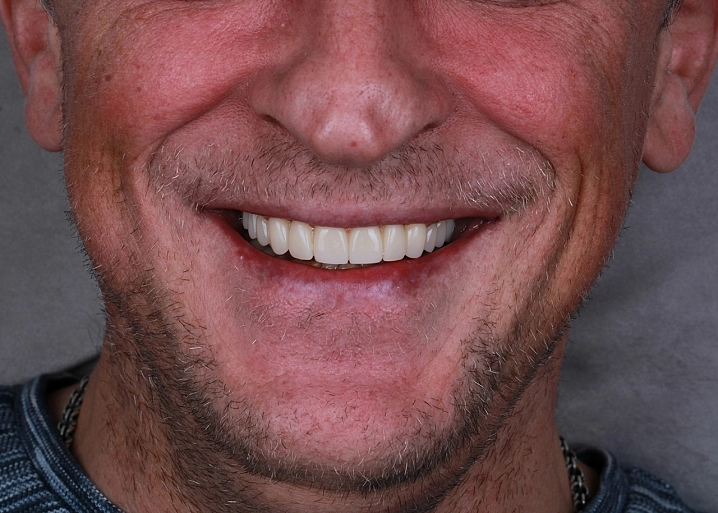

Причины и методы лечения подвижного зуба.